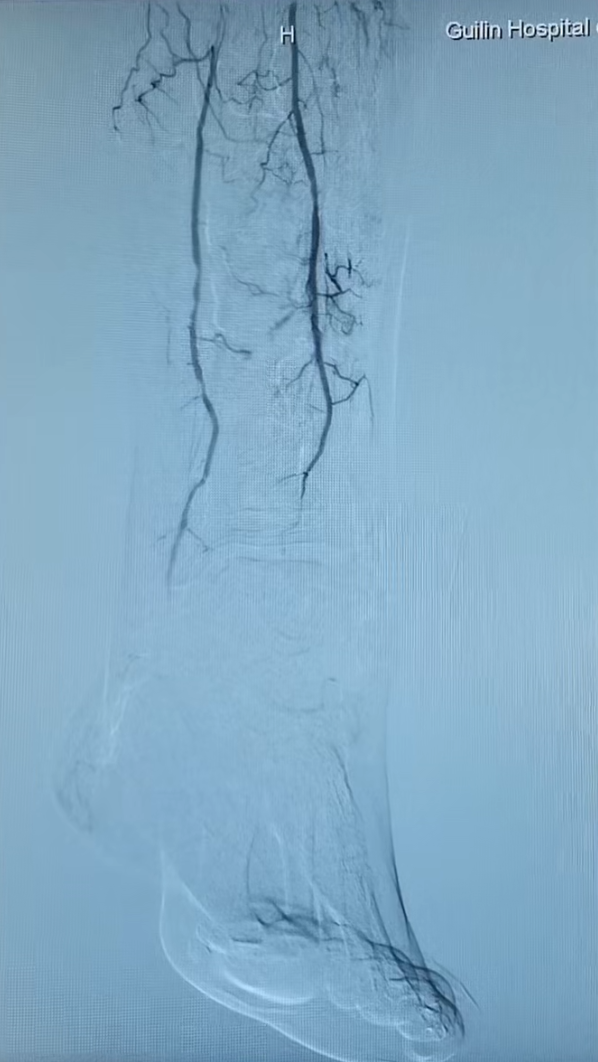

术前小腿.png

术后小腿.png

术前(左)、术后(右)小腿动脉的IVUS对比